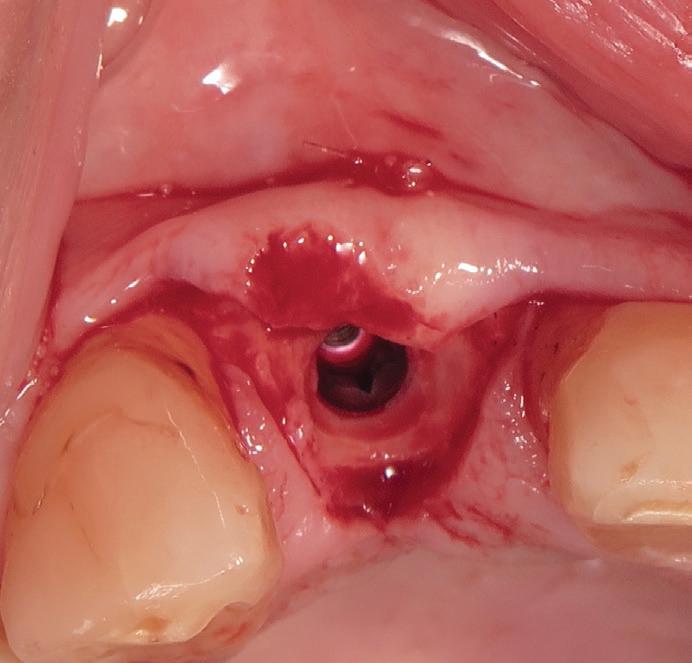

Tooth replacement from extraction to restoration. 3. Second-stage and impression procedures

The third part of this series reviews uncovering of implants that were buried in a 2-stage approach, provisionalization of the implant, and impression and scanning techniques.1 These techniques are all crucial for the final restorative outcome of the implant. The uncovering and second-stage procedures set the foundation for the shape and position of the soft tissue, which are very important esthetic factors. This information must also be properly transferred to the laboratory via a highly accurate impression so the laboratory has as much information as possible. If these steps are done properly, the result will be implant crowns that are easy to seat, biologically ideal, and esthetically pleasing.

Second-stage procedures